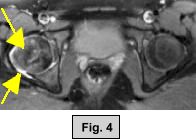

MRI FINDINGS:  The MRI was performed on AIC's high-field 1.5 Tesla short-bore Siemens Symphony.  Coronal T1 and fat suppressed turbo STIR weighted, axial proton density and T2 weighted with Fat Saturation, and sagittal DESS sequences were obtained bilaterally.  Fig. 1 (coronal T1W) shows widening and irregularity of the growth plate in the right hip.  Fig. 2 (coronal STIR) shows subtle adjacent marrow edema and moderate joint effusion.  Fig. 3 (sagittal DESS) and Fig. 4 (axial PD Fat Sat) also demonstrate the same findings.  Subtle medial displacement of the right femoral epiphysis is also noted on the coronal images.